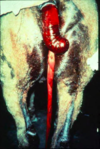

GRADE IT: Rectal Tears

Tissue Affected:

- All layers into abdomen

- May be associated with prolapse of small colon or small intestine through defect

*Horse can develop sepsis/peritonitis in relation to this tear

GRADE 4